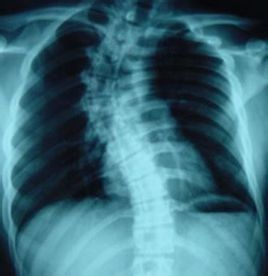

胸椎一個或數個脊椎節段向側方彎曲並伴有椎體鏇轉的脊柱畸形。

(1)側凸:即部分脊柱棘突偏離身體中線稱脊柱側彎,有左側凸、、右側凸及S形彎,C形彎。

(2)後凸:指胸段脊柱後凸超過生理曲線範圍者。脊柱側凸

(6)鏇轉性(扭曲性):是因為腰椎橫突一面高一面低或胸骨扭曲形成的,這種彎曲是最複雜,最難治的。